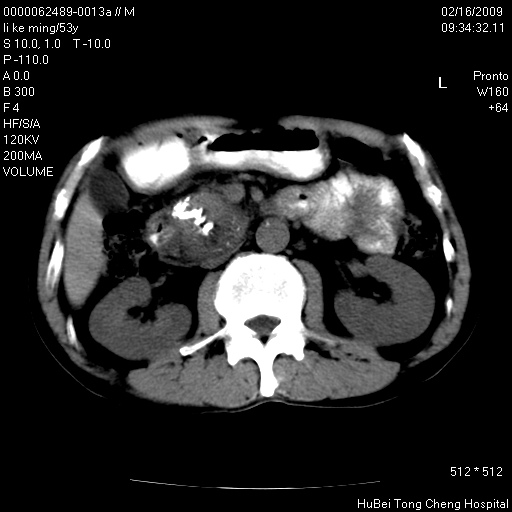

以下是引用卜一在2009-2-16 16:13:00的发言:[br]胰胆管扩张,末端明显狭窄 梗阻,胰头及十二指降段壶腹部结构紊乱。多考虑:十二指降段壶腹部癌!

以下是引用dyqct在2009-2-16 16:58:00的发言:[br]胰头内斑点状及结节状高密度影是钙化灶还是其它?以往做过什么治疗?

以下是引用zsl6918在2009-2-17 8:48:00的发言:[br]符合胰头癌侵犯十二指肠。